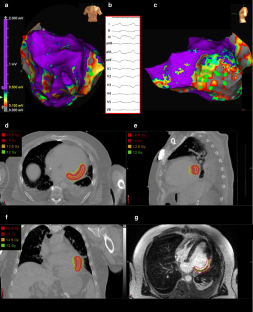

Fig. 1

Fig. 2